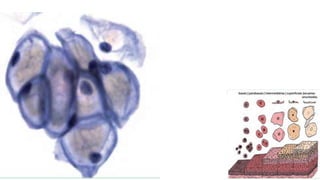

Citoplasma relativamente abundante, delicado,

semitransparente, que cora fracamente em azul, às vezes com

vacúolos.

Os núcleos são redondos ou ovais, com alguma variação do

tamanho, cromatina finamente granular exibindo cromocentros

ou nucléolo.

Quando as células são vistas de frente, elas se agrupam em

conjuntos monoestratificados, perdem a sua forma colunar e

apresentam, às vezes, bordas citoplasmáticas bem definidas,

lembrando um “favo de mel”. Os núcleos arredondados

mostram polaridade conservada (a distância entre os núcleos

é relativamente constante, não ocorrendo sobreposição

nuclear).